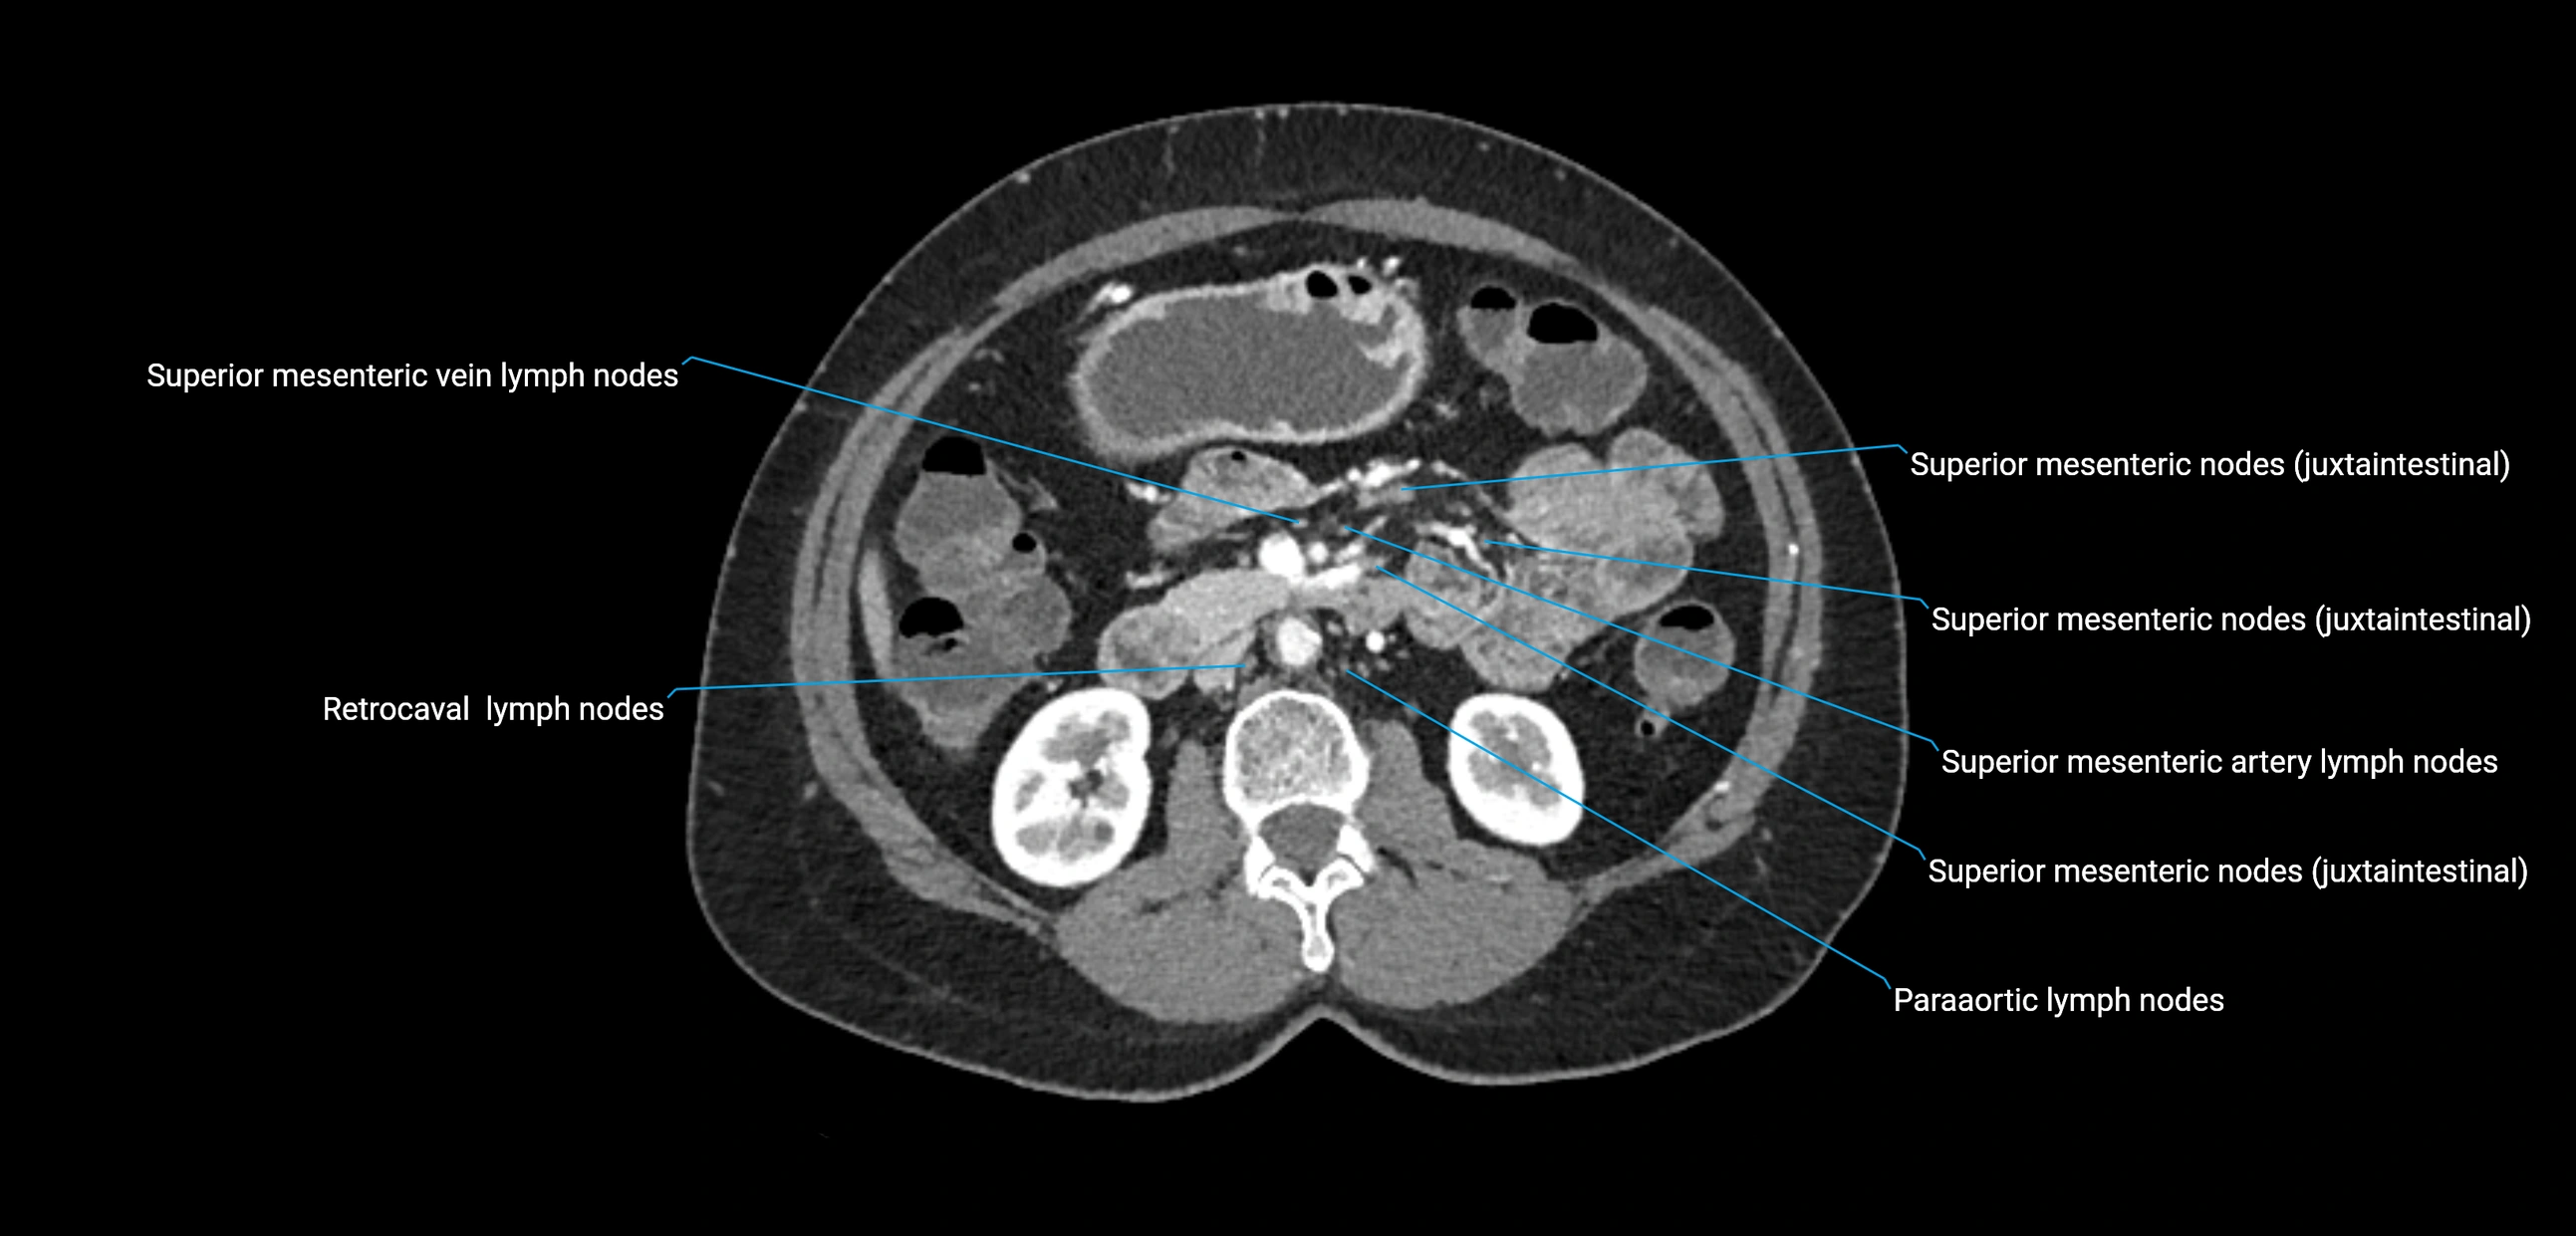

CT Appearance

CT Pre-Contrast:

• Nodes appear as soft-tissue density nodules adjacent to the aorta and IVC

• Calcification may be seen in chronic infections (e.g., tuberculosis)

CT Post-Contrast:

• Normal nodes enhance homogeneously

• Malignant nodes may show heterogeneous enhancement, central necrosis, or conglomerate formation

• Size >1 cm short axis is suspicious, though morphology and distribution are equally important

CT Venography (CTV):

• Demonstrates nodal encasement or compression of adjacent vessels (aorta, IVC, renal veins)

• Useful in staging testicular and ovarian malignancies

• Provides 3D reconstructions for retroperitoneal lymph node dissection planning